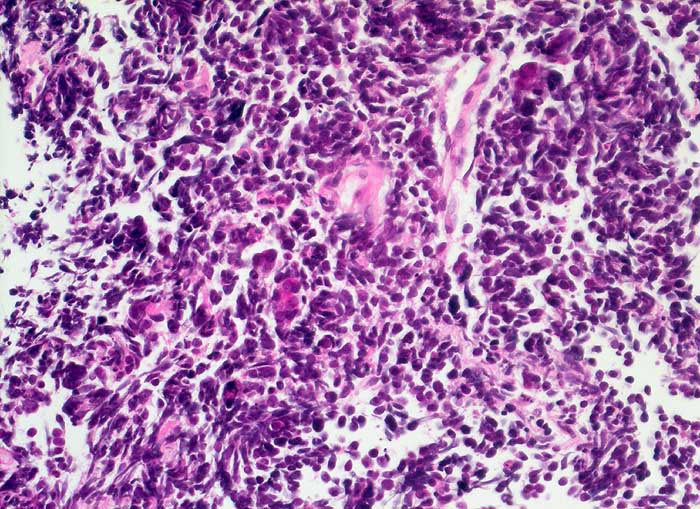

PathoPic ID 6377 - Kleinzelliges Karzinom

Kleinzelliges Karzinom

maligner Tumor

Lunge

Typischer Aspekt des kleinzelligen Tumors mit dicht gelagerten kleinen Tumorzellen mit fragilen Kernen und kaum erkennbarem Zytoplasma.

Totale Stenose des rechten Hauptbronchus mit Kompression der Vena Cava superior. Kleinzelliges Karzinom? Lymphom?

Histologie

400